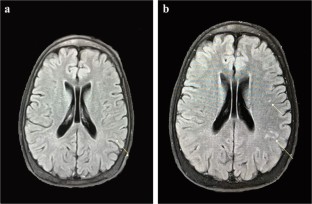

Silent brain lesions might be associated with overt cerebrovascular accident over time in beta thalassemia major (BTM) and intermediate (BTI). Aspirin may be protective in these patients. We evaluated brain magnetic resonance imaging (MRI) in thalassemia patients to see whether aspirin is protective or not. A historical cohort study was conducted on 35 thalassemia patients, 22 BTI, and 13 BTM patients at Shiraz Hematology Research Center in 2018. Median age of the patients was 32 years and ranged from 8 to 42 years. Twenty-four patients (68.6%) were females. Overall frequency of white matter lesions (WMLs) in the first MRI was 10 patients (28.6%). After 3 years, 3 patients developed new lesions and the frequency of WMLs was 13 patients (37.1%) in the second MRI. Moreover, in 3 patients, number of WMLs increased. Patients with new lesions or more lesions compared to the baseline were significantly older than the other group (median age 36.5 years vs. 31 years, P = 0.046). Regarding aspirin consumption, only 1 patient (16.7%) of patients with new lesions was using aspirin compared to 10 (34.5%) of the other group (P = 0.640). The high-risk patients with thrombocytosis, splenectomy, severe iron overload, and older age (> 30 years) should be under close follow-up and evaluated on a regular periodic basis as well as brain MRI at least once every 3 years. Aspirin could be protective against new or progressive brain lesions so that low-dose aspirin is recommended in high-risk thalassemia patients.